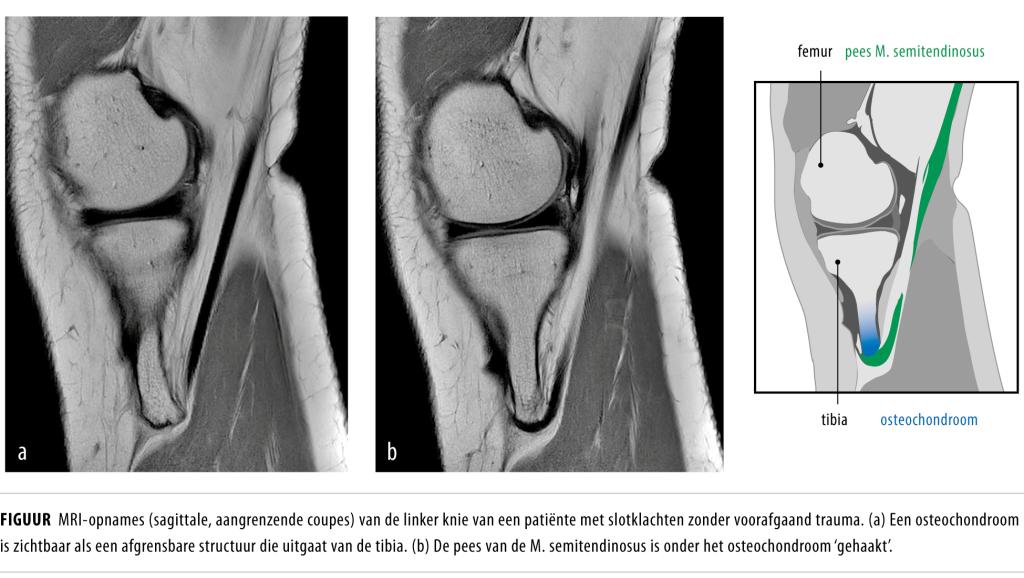

Source: cluaityle.pages.dev Knie op slot zonder voorafgaand trauma NTvG , Voorzichtige beweging: Probeer voorzichtig de knie te bewegen zonder te veel druk uit te oefenen. Het kan aanvoelen alsof er iets in de knie vastzit, waardoor het moeilijk is om normaal te bewegen